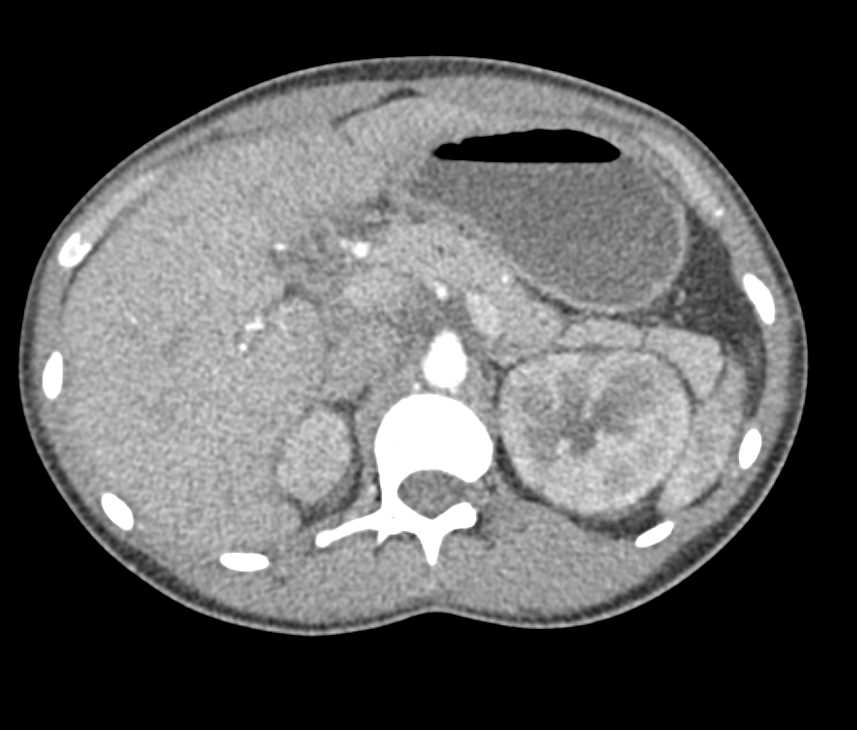

Renal Cell Carcinoma with Vascular Invasion and Infarcted Spleen